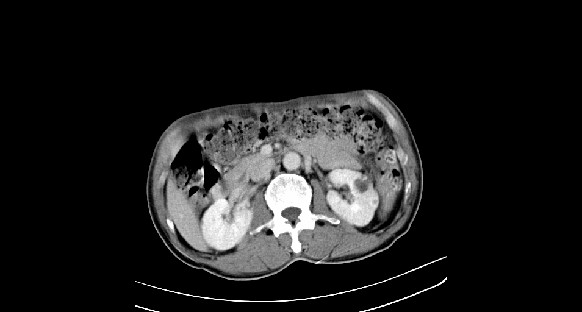

男性,70岁,体检b超发现左肾占位,请各位战友发表一下观点

左肾有两个病灶,且较大的病灶内可见点状钙化灶,增强扫描边缘也是呈渐进性强化,中央部分未见明显强化